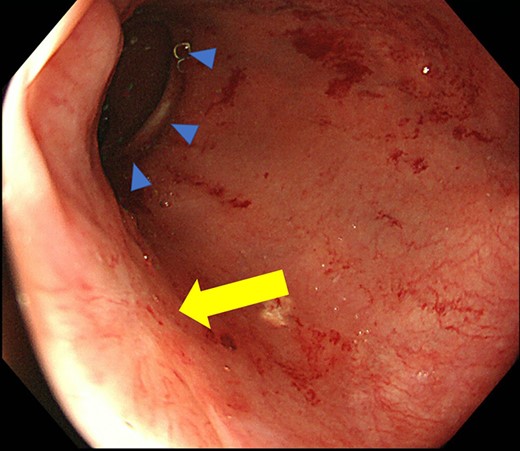

Case 1 was a 71-year-old man with a BMI of 29.7 kg/m2. Laparoscopic low anterior resection (LAR) and ileostomy was performed for rectal cancer in 2017 years. Postoperative fever and lower abdominal pain were noted, and colonoscopy was performed, and anastomotic leakage was noted with a correction of about 1/2 around the 6 o’clock direction of the anastomotic region, and fistula and formation of a large abscess cavity. After identification (Fig. 1), a tube was inserted for drainage and conservative treatment was performed. The patient was discharged on POD 46. Four months after the operation, marked improvement in the abscess cavity was noted but still remained (Fig. 2a and b). Anastomotic leakage was almost improved by colonoscopy at 17 months after surgery, but at the preference of the patient we performed colostomy 22 months after surgery (Fig. 3). It took a long time to improve intestinal movement of the colon because the large intestinal tract had not been used for a long time, and conservative treatment was performed using a nasogastric tube for paralytic ileus. Diet was initiated 7 days after surgery, and the patient was discharged from the hospital 14 days after surgery. The Wexner score [2] was 19 points one month after closure, 17 points 3 months after the operation and 16 points after 6 months after the operation, and severe anal dysfunction was observed, but gradually improved.

Colonoscopy revealed a true lumen (circle), an anastomotic site (triangle) and a cavity due to suture failure (arrow).